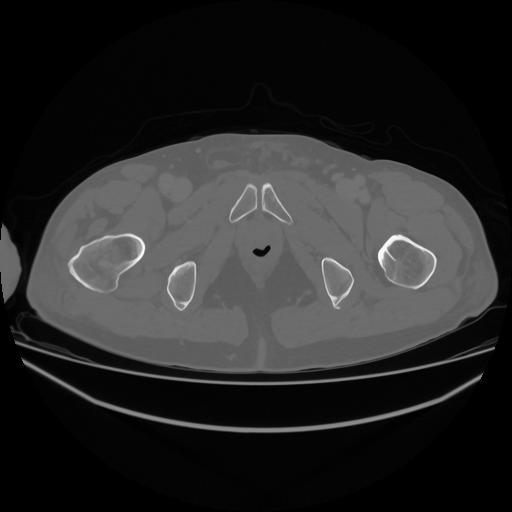

5 CUERPO,CE,Vol,1.0,CUERPO,,